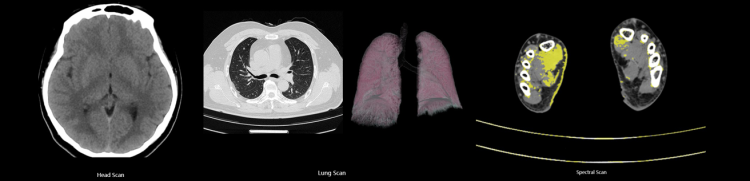

Anke ANATOM P428, optimum iş akışını sağlayabilmek ve yüksek kaliteli görüntüler verebilmek için özel teknolojilerle donatılmış 128 kesit bir bilgisayarlı tomografi sistemidir.

70 kV bakım tarama modu da dahil olmak üzere her hastaya uygun dozda bakım çözümleri sunar..

Yeni nesil OptiWave dedektörü sayesinde ALARA prensibine uygun şekilde kayıpsız ve fazlasıyla net görüntüleme performansı sunar.